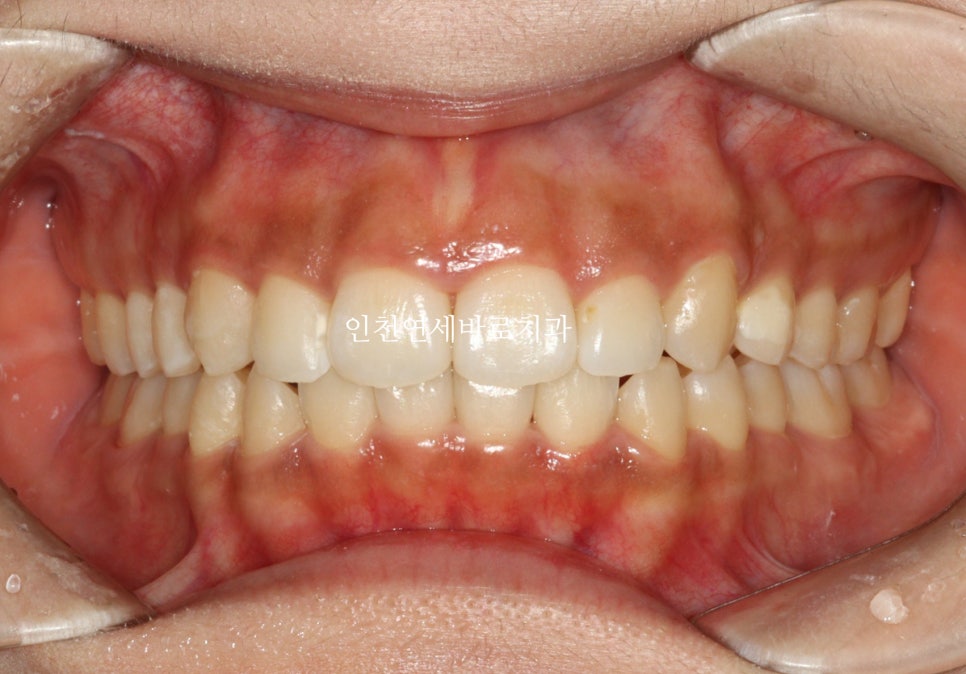

2024년 10월 – 치료 완료

2월초부터 장치를 착용했고 10월에 마무리 했습니다.

1개의 장치를 7일씩 착용하고, 중간에 재제작 한달이라는 기간이 포함된 기간입니다.

치료 전후 비교

전후 비교입니다

전 후 교합의 비교입니다.

안정적으로 교합이 형성되었습니다

교정 끝난 직후의 사진이라 아주 약간은 제 마음에 안드는 부분이 있지만